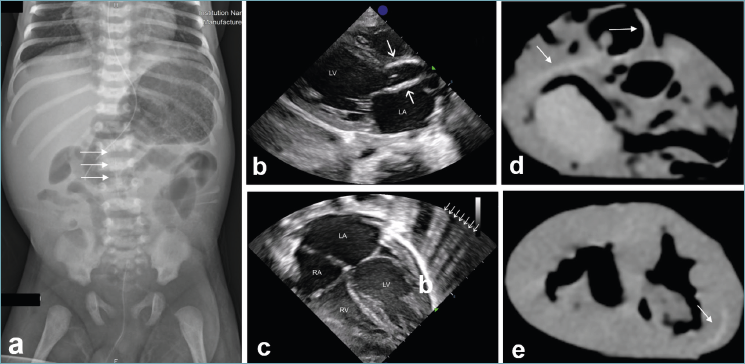

RADIOLOGICAL AND ECHOCARDIOGRAPHIC FINDINGS

Retrospective evaluation of the X-ray images performed during patient’s lifetime revealed subtle linear calcific changes predominantly affecting the lumbar segment of the aorta (Fig. 7a). Similarly, a retrospective review of echocardiographic studies performed on the fourth day of life demonstrated marked hyperechogenicity of the aortic root and ascending aortic wall, consistent with calcium deposition within the internal elastic lamina (Fig. 7b). The subcostal four-chamber view revealed the presence of the “sunburst sign,” a pattern suggestive of myocardial edema and/or fibrosis (Fig. 7c).

Post-mortem computed tomography of the formalin-fixed heart demonstrated diffuse and extensive calcification involving the coronary arteries and the aortic root (Figure 7d-e).

Figure 7. Subtle calcific deposits primarily affecting the lumbar segment of the aorta, as indicated by arrows (a). Day 4 echocardiogram (b-c): Parasternal long-axis view showing hyperechogenic walls of the aortic bulb and ascending aorta due to calcium deposits. (b) Subcostal four-chamber view demonstrating dilation of the left atrium and ventricle. White arrows indicate the “sunburst sign,” correlating with fibrosis of the left ventricular wall (c). Post-mortem computed tomography (CT) of the formalin-fixed heart demonstrated diffuse and extensive calcification (arrows) involving the coronary arteries and the aortic root (d-e).